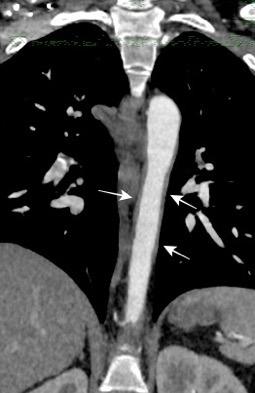

Grupos:

1. Obstrucción por encima de la V Ácigos. (La sangre llega al corazón a través de ella)

2. Obstrucción con participación de la V. Ácigos. (La sangre utiliza otras alternativas para llegar al corazón vía VCI).

Participación de la V. Ácigos como vía principal para llegar a la VCI.

Visible: 88%